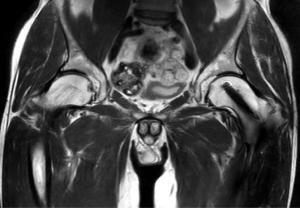

Jestem pod ogromnym wrażeniem wielkiego potencjału rozwiązania SmartSpeed, zwłaszcza w przypadku obrazowania 3D układu mięśniowo-szkieletowego, które staje się teraz możliwe. Krótki czas skanowania i świetna jakość obrazów to podstawa w prywatnym ośrodku diagnostyki obrazowej takim jak nasz”.

Dr Tobias Schröter

MRT-Praxis w Poczdamie, Niemcy